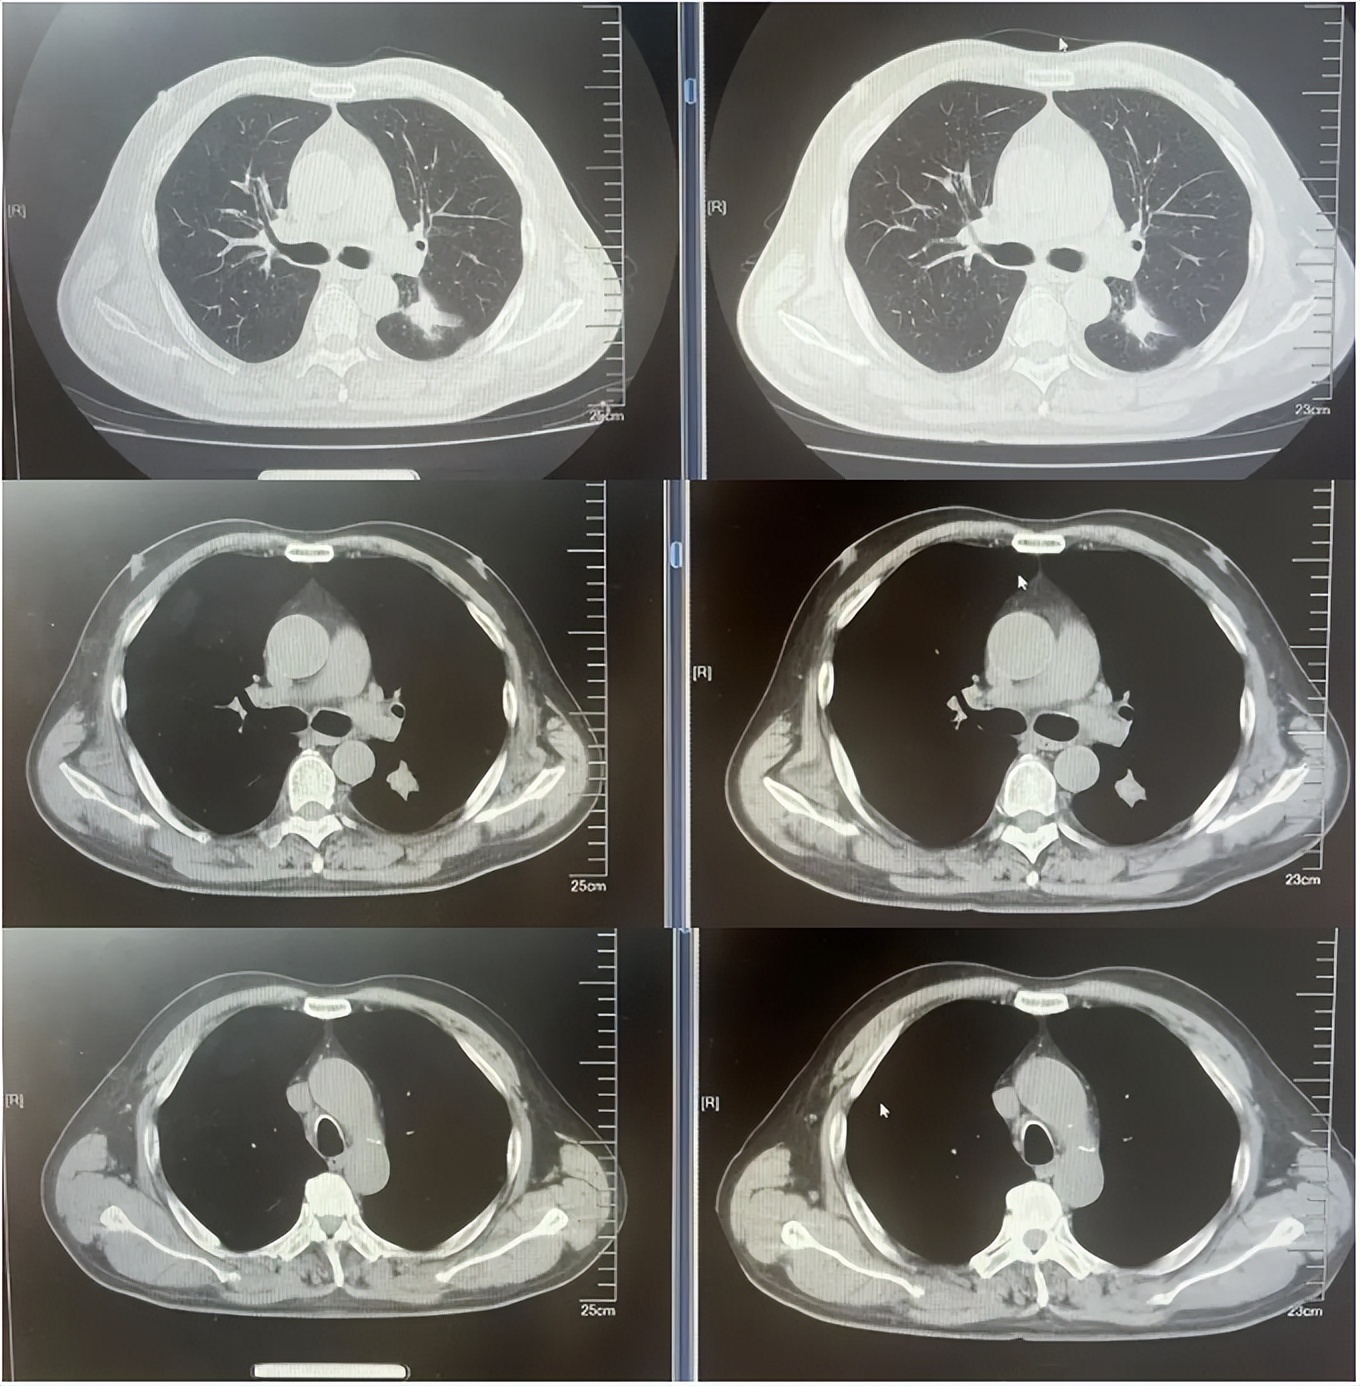

病例2:患者男,61岁。2023年8月于外院行肺CT提示:右肺下叶肿块。2023年10月23日于我院行单孔胸腔镜下右肺下叶切除术、肺门纵隔淋巴结扩清术。术后病理:腺癌低分化(腺泡型占30%,乳头型占30%,筛状占30%,微乳头占10%)。分期pT4N0M0 IIIA期。术后行基因检测提示HER2+(14%),PD-L1 2%+。术后行AC方案化疗4周期后行阿替利珠单抗维持治疗1年。末次用药时间:2024年11月1日。2025年2月复查肿瘤标志物升高,肺HRCT示:双肺多发结节,考虑转移。行血液基因检测提示:ERBB2 35.5%突变,CDK1 9.5%突变,MDM2 4.92%突变。患者DFS 14m,阿替利珠单抗停药后3个月出现复发转移,可见传统免疫治疗效果不佳。恰逢德曲妥珠单抗一线新尝试DESTINY-lung 04研究公布了入组标准和治疗方案,且该患在术后的组织基因检测和复发后的血液基因检测中都明确存在HER2突变,故行德曲妥珠单抗一线治疗。最佳疗效PR,目前治疗持续有效,PFS超过6个月。无药物相关不良反应发生。

德曲妥珠单抗治疗4周期(2025.4)疗效对比